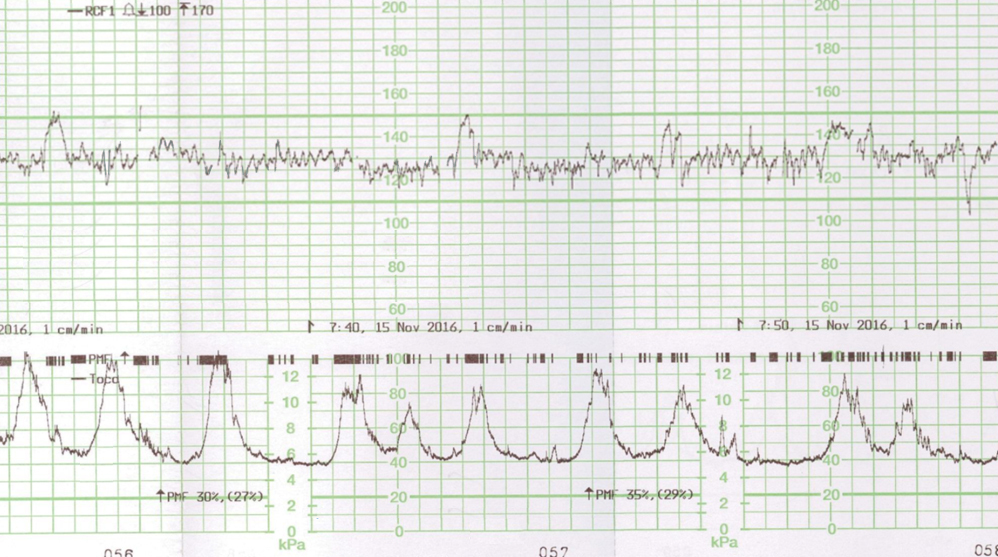

Voici le résultat de la cardiotocométrie et de l’échographie du col réalisée par voie endovaginale.

Figure 4 (Rodolphe Matias de Sousa, La Revue du Praticien)

Une menace d’accouchement prématuré se définit comme des contractions utérines régulières et douloureuses (ici 5 par dix minutes visibles à la tocométrie) et un col raccourci ou modifié cliniquement (ici mesuré à 20 mm à l’échographie endovaginale). Un col non modifié est dit long, tonique, postérieur, fermé avec une présentation fœtale non sollicitante.

Concernant l’analyse du rythme cardiaque fœtal.

Un rythme cardiaque fœtal normal a :

– un rythme de base entre 110 et 160 bpm ;

– des accélérations correspondant à une augmentation du rythme cardiaque fœtal de plus de 15 bpm pendant au moins 15 sec ;

– une variabilité correspondant à des oscillations du rythme cardiaque fœtal entre 5 et 25 bpm ;

– l’absence de ralentissement.